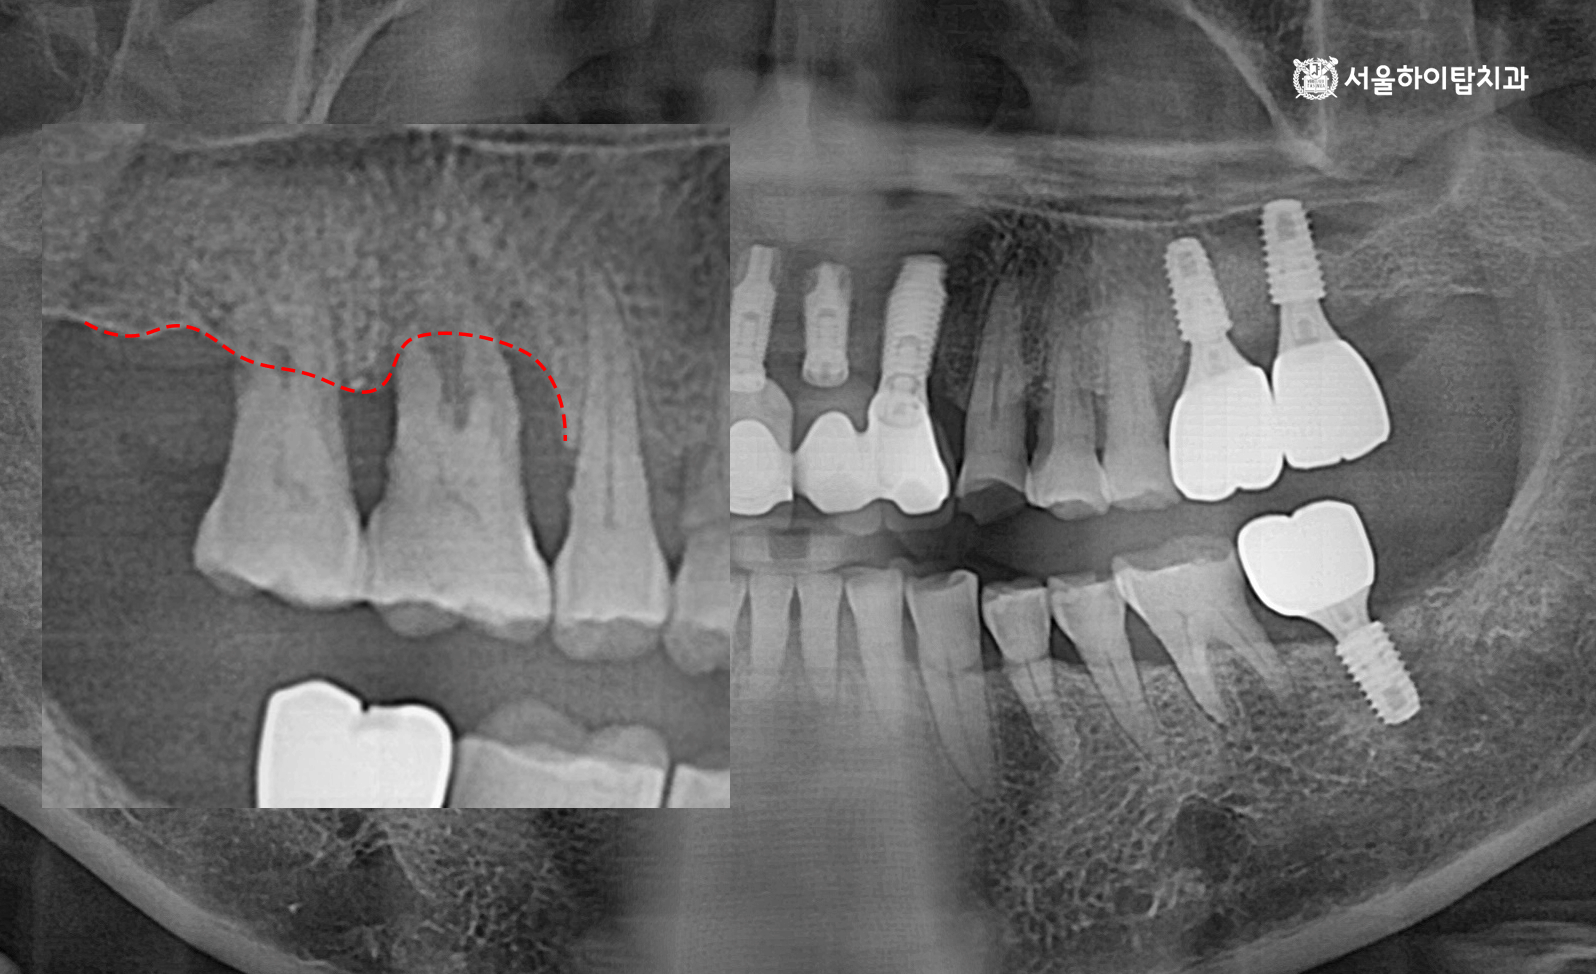

십정동 치과 상실된 치아가 불러오는 연쇄적 문제? 치조골 흡수와 기울어진 어금니, 뼈이식 동반 임플란트 과정 동암역 치과 : 균형 잡힌 저작이 중요한 이유, 전반적으로 손상된 치아 및 잇몸 임플란트를 통해 저작 기능 개선 간석역 치과 치주염으로 인한 치조골 흡수, 치아 파절 및 마모까지 임플란트 가상 시뮬레이션을 통한 안전한 수술 과정 1 2 Next Archives 2026년 4월 2026년 3월 2026년 2월 2026년 1월 2025년 12월 2025년 11월 Categories 미분류 신경치료 심미 치료 임플란트